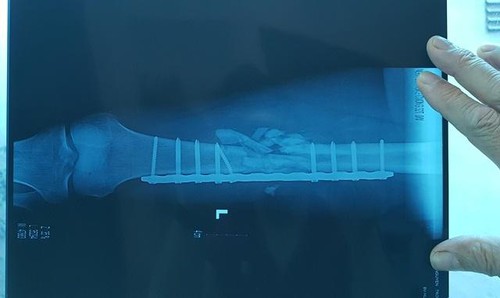

Anh Cường đã được phẫu thuật kép xương đùi sau khi bị bắn

“Khi đến, con tôi đang trong tình trạng hôn mê, xương đùi vỡ nát, vỡ động mạch… các bác sĩ yêu cầu gia đình chuyển con ra BV Việt Đức cấp cứu vì nguy hiểm đến tính mạng.

Hình ảnh xương đùi vỡ nát